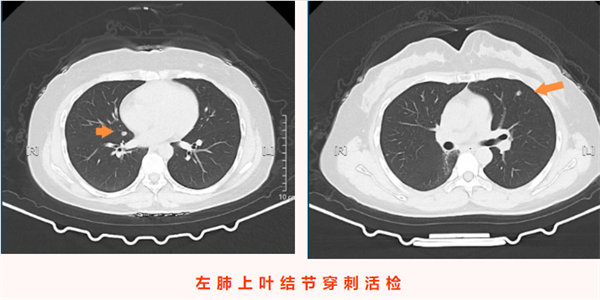

2025年11月24日,王女士的復查影像學檢查顯示:左肺上葉上舌段可見一大小僅0.8cm×0.5cm的微小實性結節,右肺斜裂處可見一0.7cm×0.6cm的實性結節,均為較前新增病灶。結合患者六年前氣管腺樣囊性癌病史,高度懷疑為轉移瘤。由于病灶性質不明且存在轉移可能,王女士為求進一步精準診療來到我院胸心腫瘤外科,門診以“左肺上葉繼發惡性腫瘤”將其收入院。值得注意的是,患者此次就診全程無咳嗽咳痰、發熱寒戰、胸悶氣短等任何典型癥狀,完全是通過規律復查發現的早期病灶,為后續干預贏得了有利時機。

入院后,醫療團隊結合患者既往腺樣囊性癌病史、影像學檢查結果,術前綜合評估后高度懷疑雙側肺結節為腫瘤轉移灶。考慮到患者無明顯癥狀、病灶相對局限,為最大限度減少患者創傷、避免二次手術,團隊決定為其同期實施雙側肺結節診療手術——即CT引導下經皮左肺上葉微小結節穿刺活檢+微波消融術,同期對右肺結節行微波消融術。手術由科主任陳瑜主刀,副主任吳明君擔任助手,魏寶、張寶軍為第二助手。手術過程中,醫師團隊首先聚焦左肺上葉僅0.8cm×0.5cm的微小實性結節,在左側腋下及前外側胸壁精準標記,在患者平靜呼吸狀態下通過CT反復掃描確認穿刺參數,成功獲取活檢組織。并按計劃對左肺穿刺后的結節及右肺斜裂結節同期實施微波消融術,精準破壞雙側病灶組織。整個手術過程一氣呵成,同期完成雙側病灶診療,術中患者生命體征始終平穩。

術后,患者安返病房,生命體征穩定,無胸痛、咯血、氣胸等不適癥狀,飲食睡眠恢復良好。術后病理結果回報,明確左肺上葉結節為腺樣囊性癌轉移灶,與術前評估判斷一致,為后續診療方案制定提供了金標準依據。本例患者無任何癥狀,正是通過定期復查實現轉移病灶的早期發現;同時彰顯了“診斷+治療”一體化微創技術的臨床價值,為惡性腫瘤轉移灶的早期干預提供了高效、精準的診療范式,有力保障了腫瘤患者的長期生存質量。